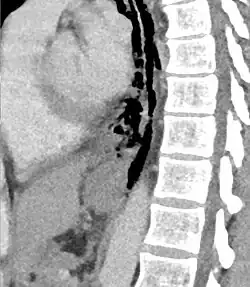

Sagittal reformatted CT image showing discontinutity in the wall of the posterolateral aspect of the distal esophagus

The diagnosis of Boerhaave syndrome is suggested on the plain chest radiography and confirmed by chest CT scan. The initial plain chest radiograph is almost always abnormal in patients with Boerhaave syndrome and usually reveals mediastinal or free peritoneal air as the initial radiologic manifestation. With cervical esophageal perforations, plain films of the neck show air in the soft tissues of the prevertebral space.

Hours to days later, pleural effusion(s) with or without pneumothorax, widened mediastinum, and subcutaneous emphysema is typically seen. CT scan may show esophageal wall edema and thickening, extraesophageal air, periesophageal fluid with or without gas bubbles, mediastinal widening, and air and fluid in the pleural spaces, retroperitoneum or lesser sac.